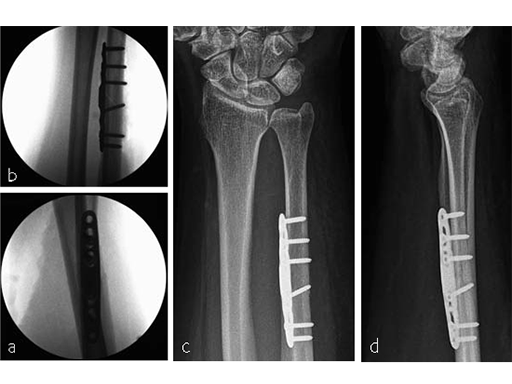

A 69-year-old female patient had suffered a right distal radius fracture one year earlier, and received conservative management. Symptoms included pain and impaired function about the wrist and forearm, with decreased forearm rotation. Painful DRUJ (DASH: 34, PWRE: 29).

Ulna impaction syndrome (or ulnocarpal abutment syndrome) is a degenerative condition related to excessive load bearing across the ulna aspect of the wrist, which results in chronic impingement of the ulna head against TFCC, lunate and triquetrum. This chronic impingement can cause wrist pain, swelling, limited range of motion and diminished grip strength. In most cases, a positive ulna variance causes ulnocarpal impaction syndrome. Distal radius fractures with radius collapse are also a common problem with a secondary painful positive ulna variance. Depending on stage and patient symptomatology, the treatment includes an ulna shortening osteotomy although common complications can include hardware irritations and delayed or non-unions.

In summary, the LCP Ulna Osteotomy 2.7 system leads to a lower complication rate, reduced non-union rate, and reduced postoperative pain, as it allows for a shorter incision, more precise cutting, better alignment, and minimizes hardware irritation, which greatly reduces the need for plate removal, if the correct surgical technique is followed.